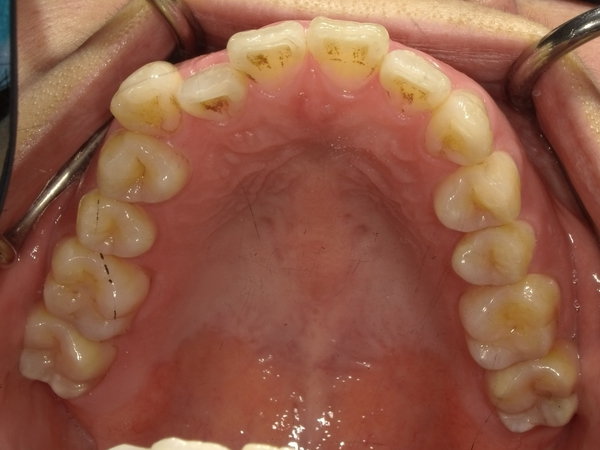

ガタガタとした歯並びや八重歯(叢生)CASE7